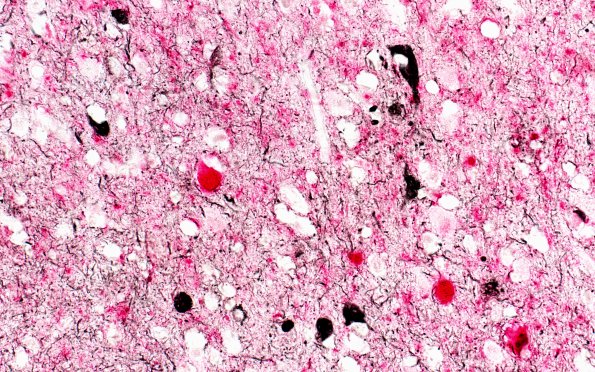

Washington University Experience | NEURODEGENERATION | Lewy Body Disease (LBD) | 4 LBD - Gross Pathology - LBD-Dementia with AD | 3B1 AD & DLBD (Case 3) (pSYNred PHFBlack)) 40X 1

3B1-4 These images represent simultaneous immunostaining of the hippocampus for alpha-synuclein (Red) and phosphorylated tau using PHF-1 (Black). ---- 3B1-3 These images show staining of spherical Lewy bodies and Lewy neurites. Black cytoplasmic neurofibrillary tangles are seen in pyramidal neurons and as cortical neurites.